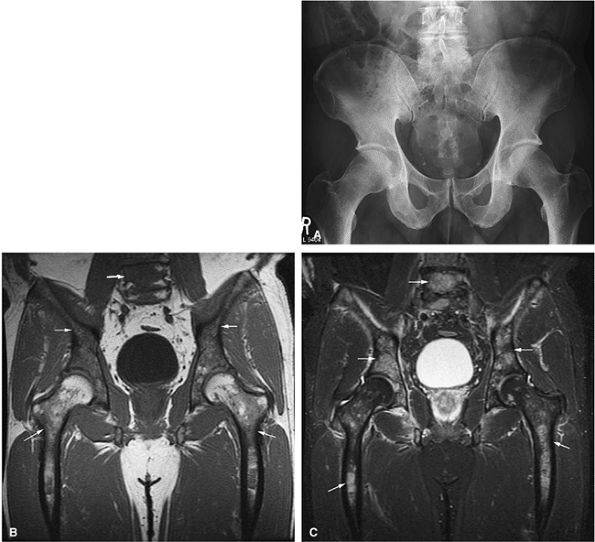

![]() |

FIGURE 13.36 ● (A) An anteroposterior radiograph of the pelvis is negative for lymphomatous involvement. (B) On a T1-weighted coronal image of the pelvis, the proximal femurs and lower lumbar spine (arrows) display nonspecific low signal intensity. The fatty marrow of the epiphysis and greater trochanter is spared. (C) On a coronal STIR image, there is high-signal-intensity patchy nodularity of lymphomatous marrow involvement in the pelvis, proximal femurs, and lumbar spine (arrows). The spared yellow marrow of the greater trochanter and femoral epiphysis appears black.